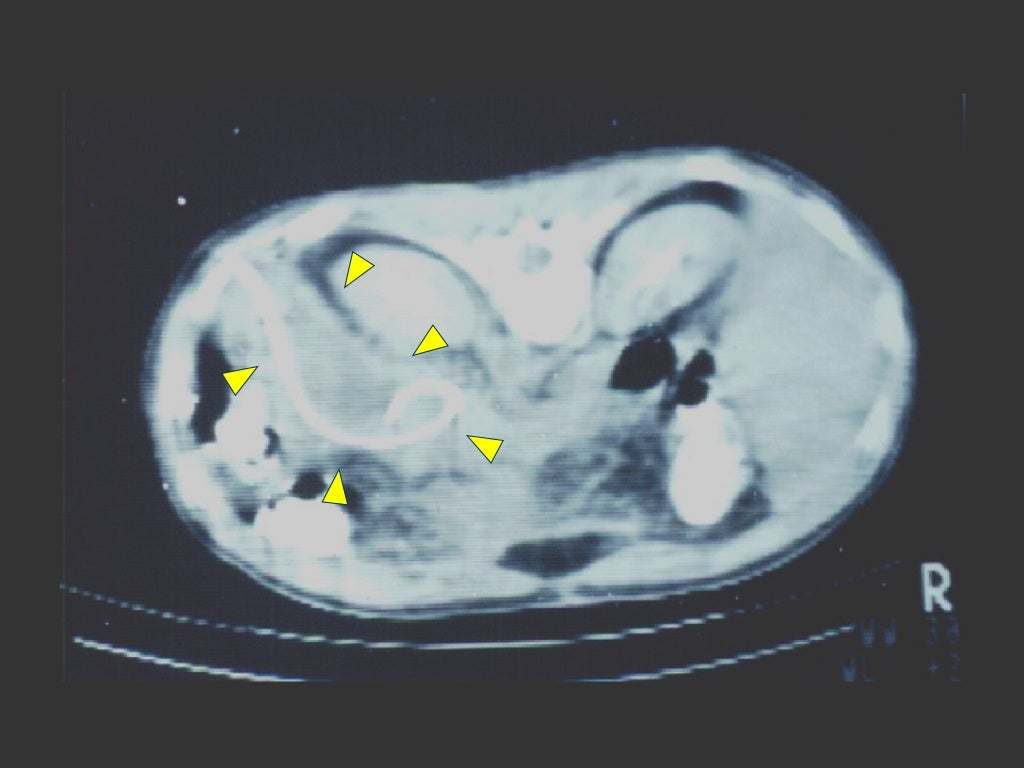

A missed case of intraabdominal sepsis BMJ Case Reports

Source: casereports.bmj.com